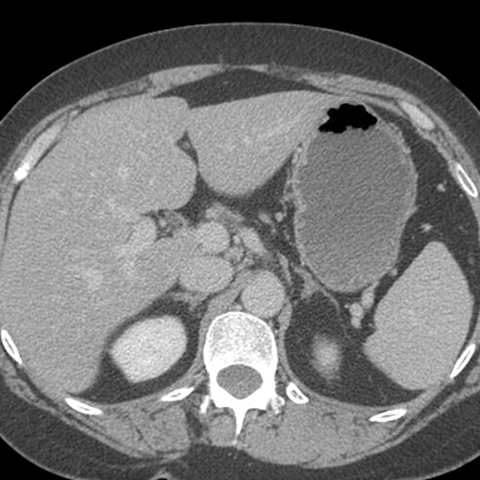

Normal Stomach, axial CT [2 of 4]